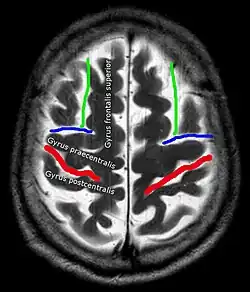

In der Computertomographie und Magnetresonanztomographie ist für die korrekte Lokalisation eines Befundes eine sichere Identifikation des Sulcus centralis oft einer der ersten Schritte. Hierfür haben sich in Abhängigkeit von der Schnittebene verschiedene Strategien etabliert.[4] Beispiele:

| Axial | Sagittal |